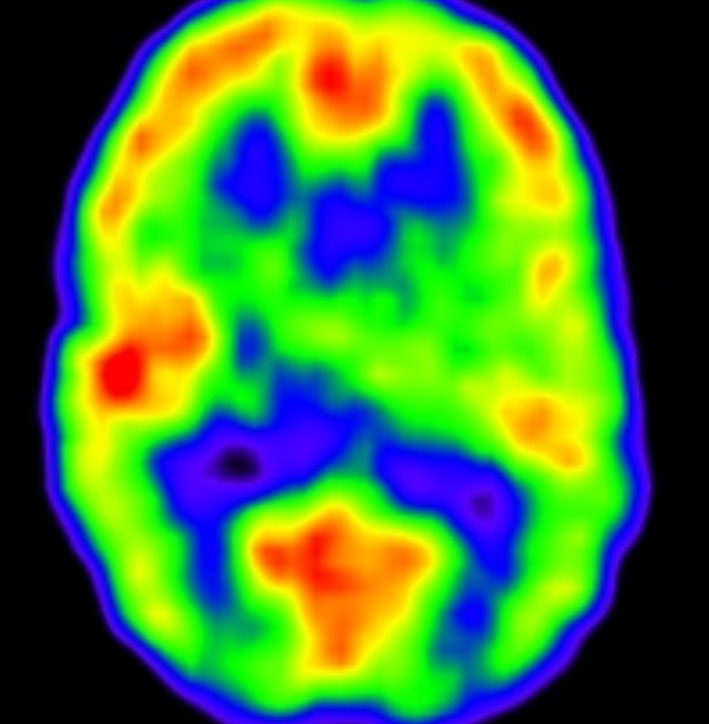

この画像は14歳の時のものです。大脳の萎縮は全くなく,小脳のダメージは最小限です。内分泌障害も無く甲状腺ホルモンも補充していませんが,背骨の伸びが悪いです。

5歳時 FIQ 79, VIQ 79, PIQ 85

14歳時 FIQ 75, VIQ 86, PIQ 68

神経心理学的検査からは,知能低下,記憶障害,注意障害があると診断されました。言語理解IQ 86,知覚統合IQ 71,注意記憶IQ 76,処理速度IQ 72です。全脳照射の18グレイばかりではなく,発症時の水頭症や小脳のダメージによる学習障害も加わっているのかもしれません。問題となってくるのは小学校高学年からですから,かなり長期的な観察が必要です。多くのお医者さんはせいぜい治療が終わってから自分では数年の観察しかしないので,治療を担当する先生がこのようなことを知らない可能性があります。